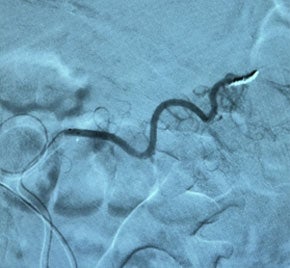

GI bleed embolized with EMBOLD™ Fibered Coils

In this case study, we show the management of a gastrointestinal (GI) bleed utilizing Embold Fibered Coils. The patient presented with symptoms, and a positive nuclear medicine scan indicated a bleed within the transverse colon. Employing a TruSelect™ Microcatheter, the medical team navigated the tortuous 2 mm distal branch, originating from the superior mesenteric artery (SMA) feeding the site of the bleed. Through the placement of two 2x4 Embold Fibered Coils, hemostasis was achieved, ultimately sparing the patient from an open surgical procedure.

A TruSelect Microcatheter was used to navigate the distal, 2 mm tortuous distal branch coming off the superior mesenteric artery (SMA) feeding the transverse colon, which was embolized with two 2x4 Embold Fibered Coils causing hemostasis.

300x300 After Embold Fibered placement​